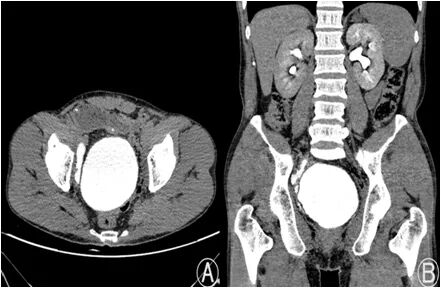

▲叶大爷术后复查情况良好